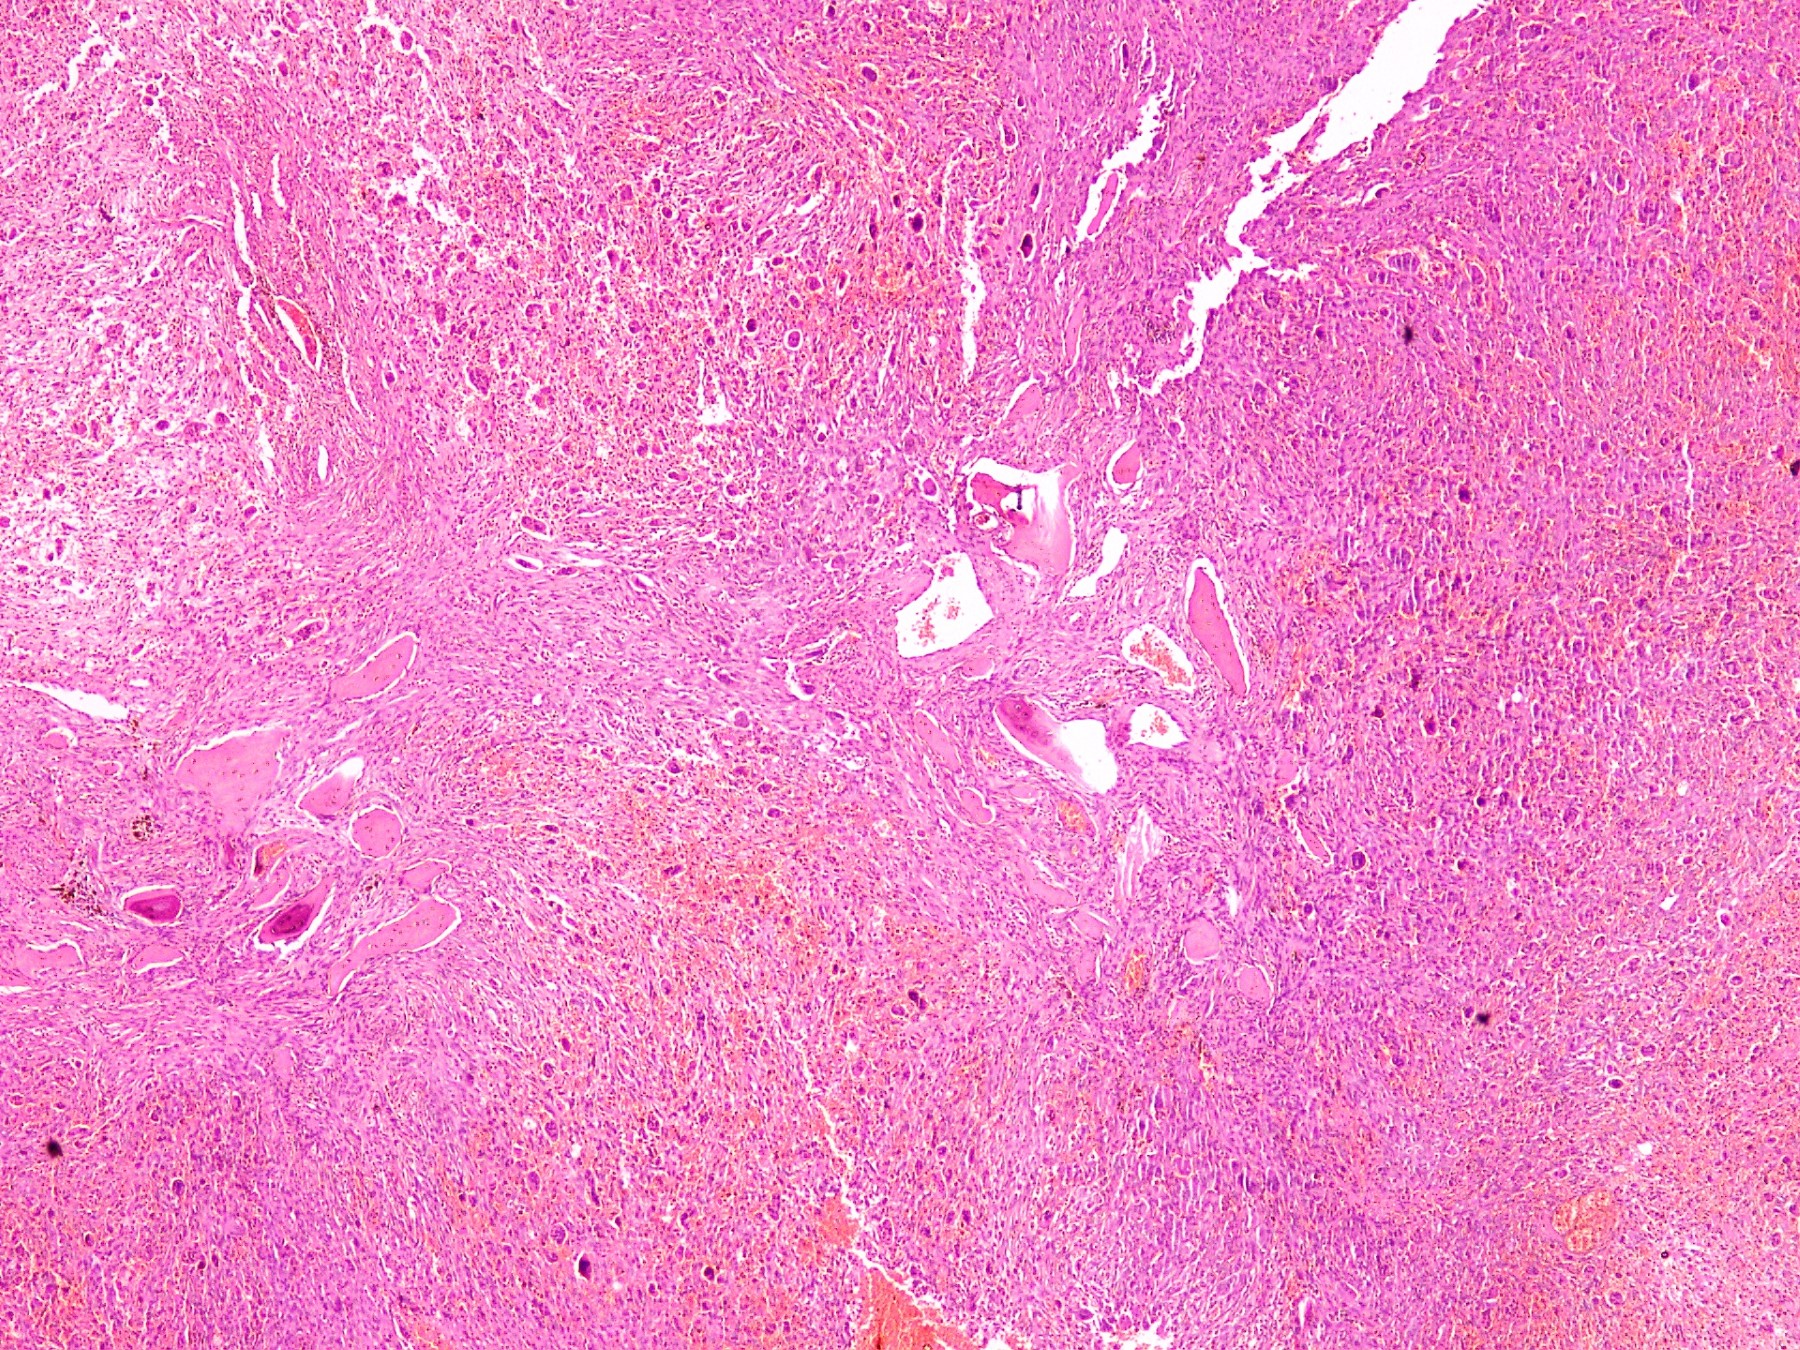

Microscopic (histologic) description

- Lobular pattern composed of groups and clusters of osteoclast-like multinucleated giant cells

- Vascular fibroblastic stroma

- Hemorrhage and hemosiderin deposits

- Tunneling resorption of adjacent uninvolved bone (J Int Oral Health 2015;7:50)

Microscopic (histologic) images

- Giant cell rich lesion (see comment)

- Comment: The lesion is composed of clusters of giant cells in a hemorrhagic fibroblastic stroma. Focal tunneling bone resorption is seen. This feature, along with multiple lytic lesions on radiology, strongly favor brown tumor of hyperparathyroidism. Correlation with clinical history, radiological findings and serum PTH and calcium levels is recommended.

D. End stage renal disease. The photomicrograph shows a lesion composed of scattered osteoclast-like giant cells in a vascularized spindled stroma characteristic of brown tumor of hyperparathyroidism. End stage renal disease causes decreased glomerular filtration due to reduced nephron function, which results in decreased synthesis of 1,25 dihydroxyvitamin D3 by the kidney. This leads to decreased absorption of calcium by the gut. Consequently, there is an increased level of serum phosphate. Increased serum phosphate causes serum calcium to be deposited in bone, also leading to a decreased serum calcium. In response to low serum calcium levels, the parathyroid glands secrete increased parathyroid hormone, which results in secondary hyperparathyroidism.